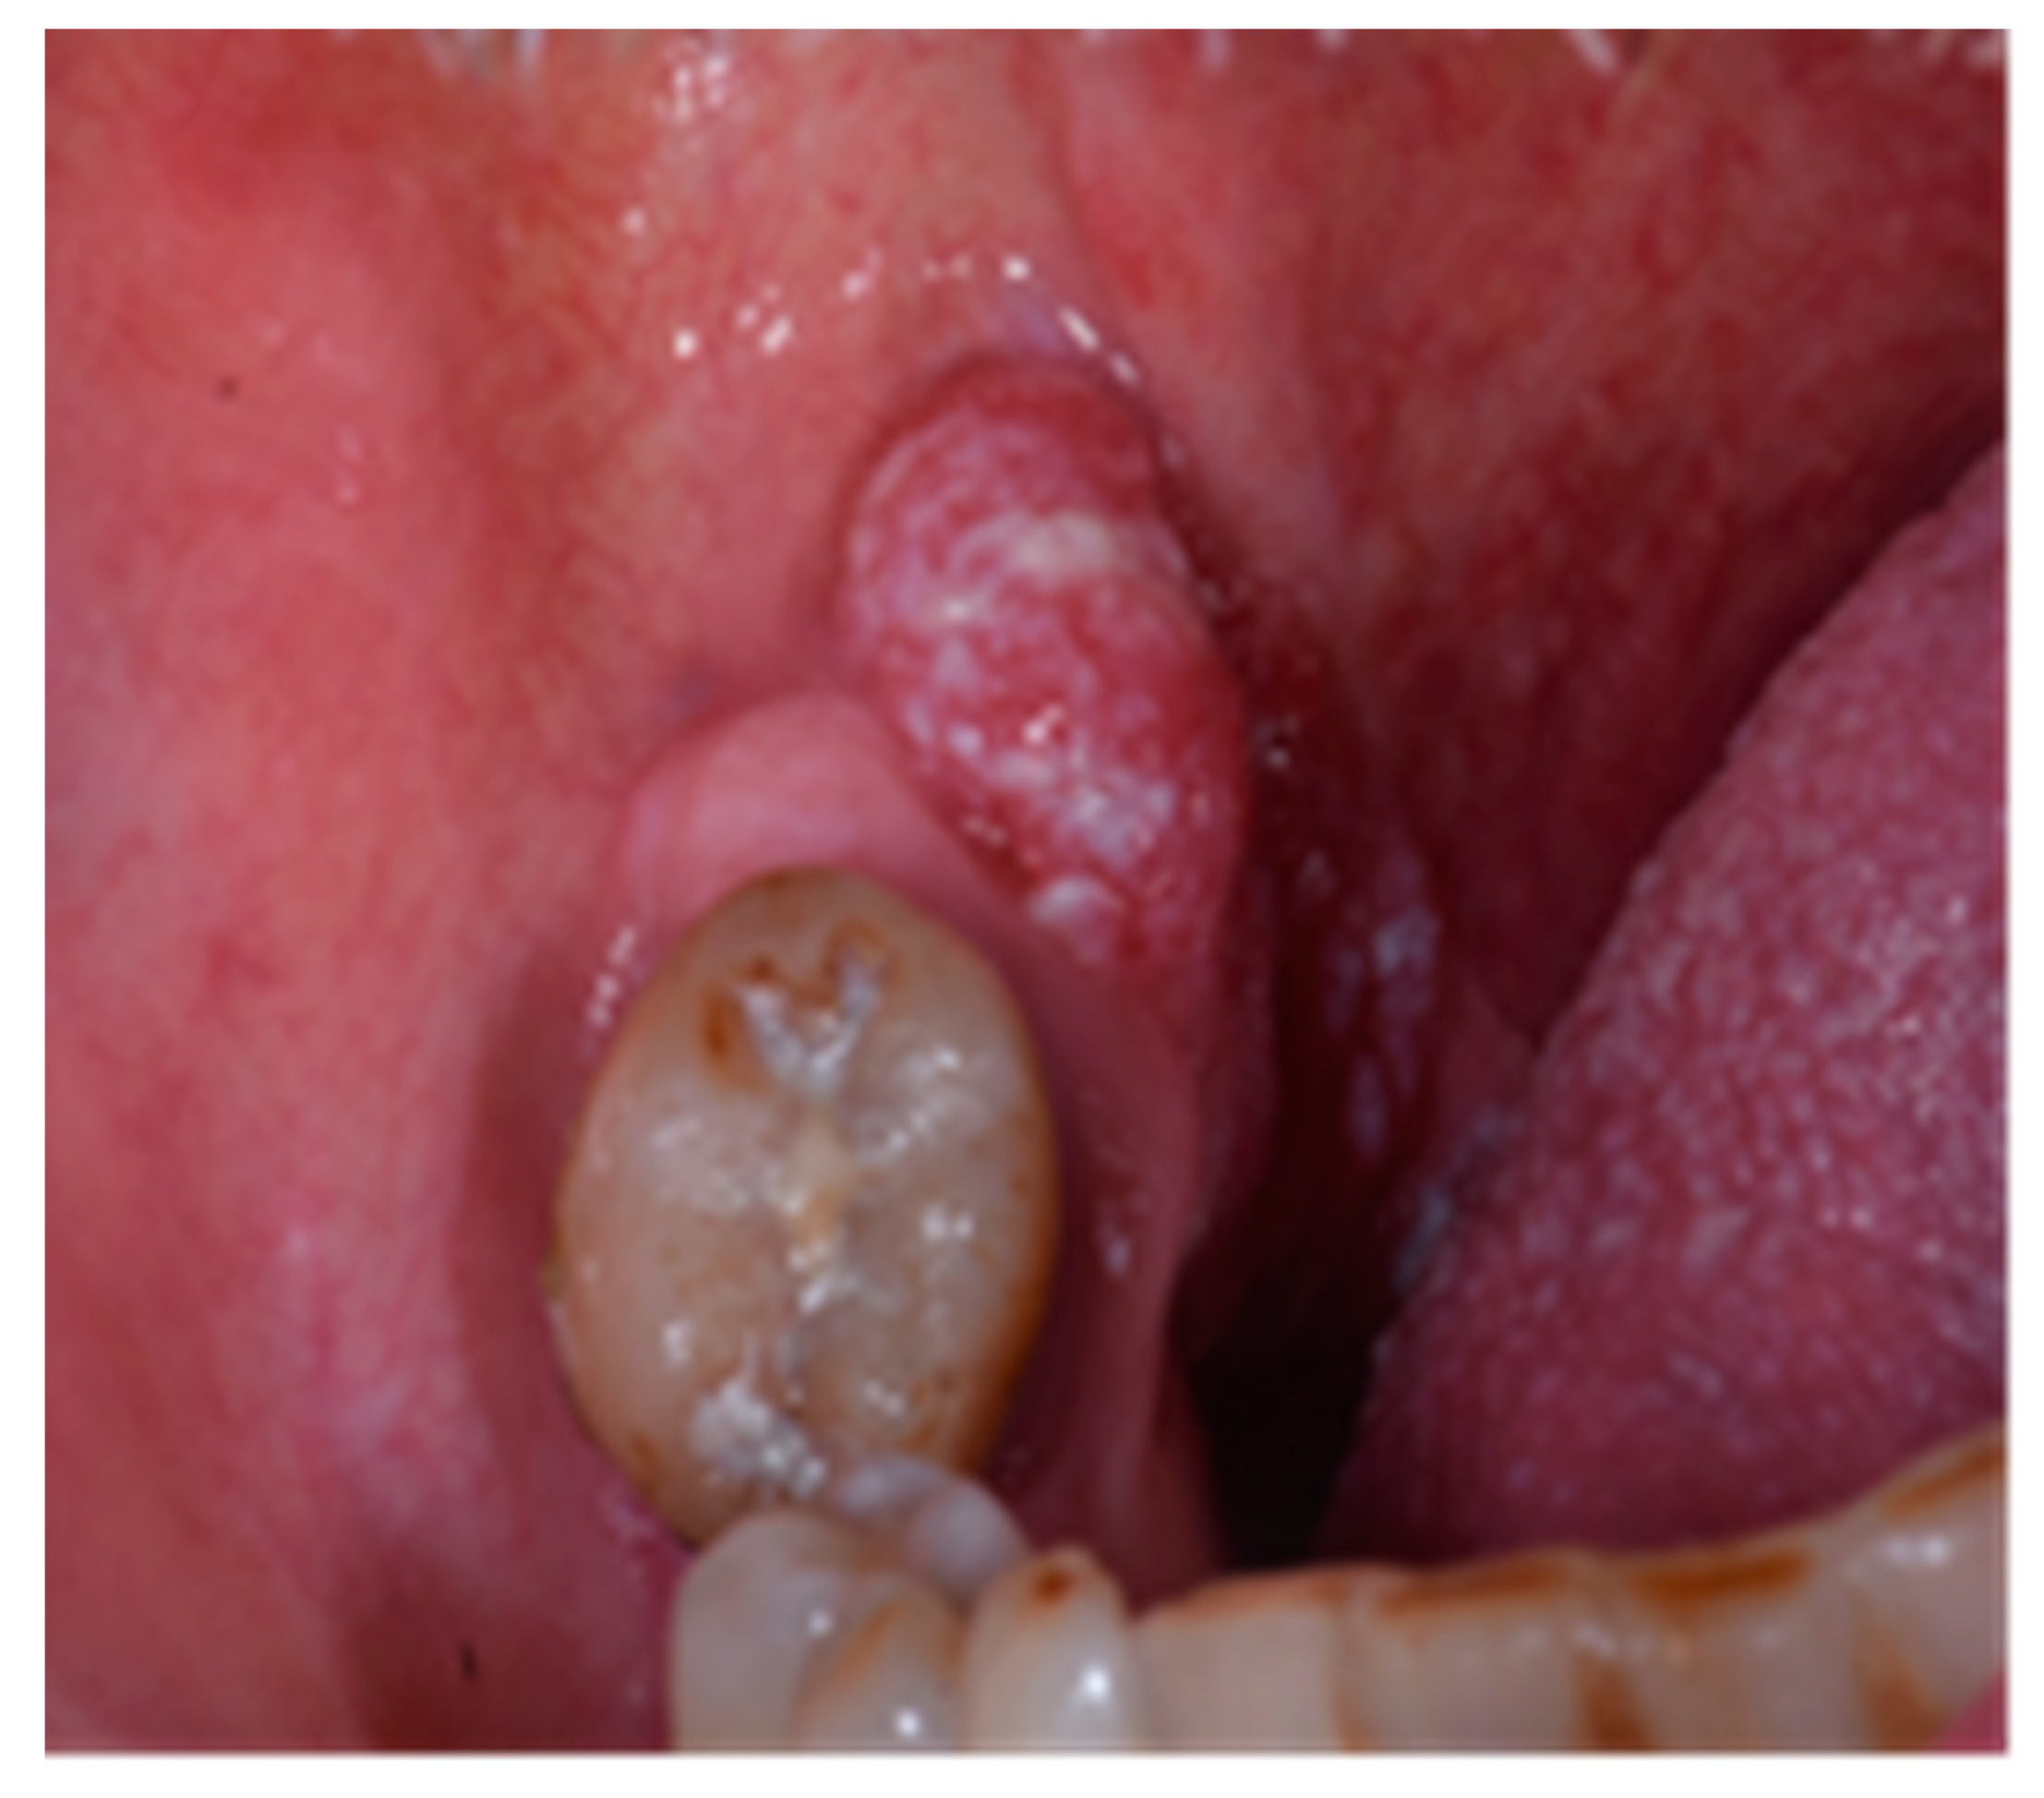

HPV-DNA Positive/p16 IHC Negative Oral Squamous Cell Carcinoma: A Case Report †

2. Case Report